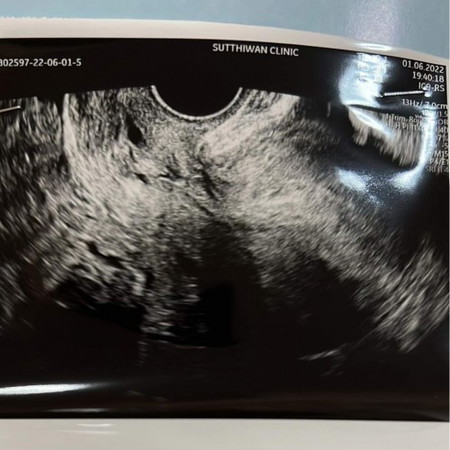

เราไปซาวตอน 4 สป ไม่เจออะไีร เจอแต่ผนังมดลูกหนาขึ้น คุณหมอนัดอีกทีตอน7สปค่ะ ขอประสบการณ์แม่ๆที่ซาวน์ตอน สี่ สัปดาห์ด้วยค่ะ

เจอตอนสี่วีคค่ะ แต่น้องตัวเล็กมากๆ พอไปซาวด์ 6 วีค ขนาดตัวยังแค่ 0.88 ซม.เองค่ะ